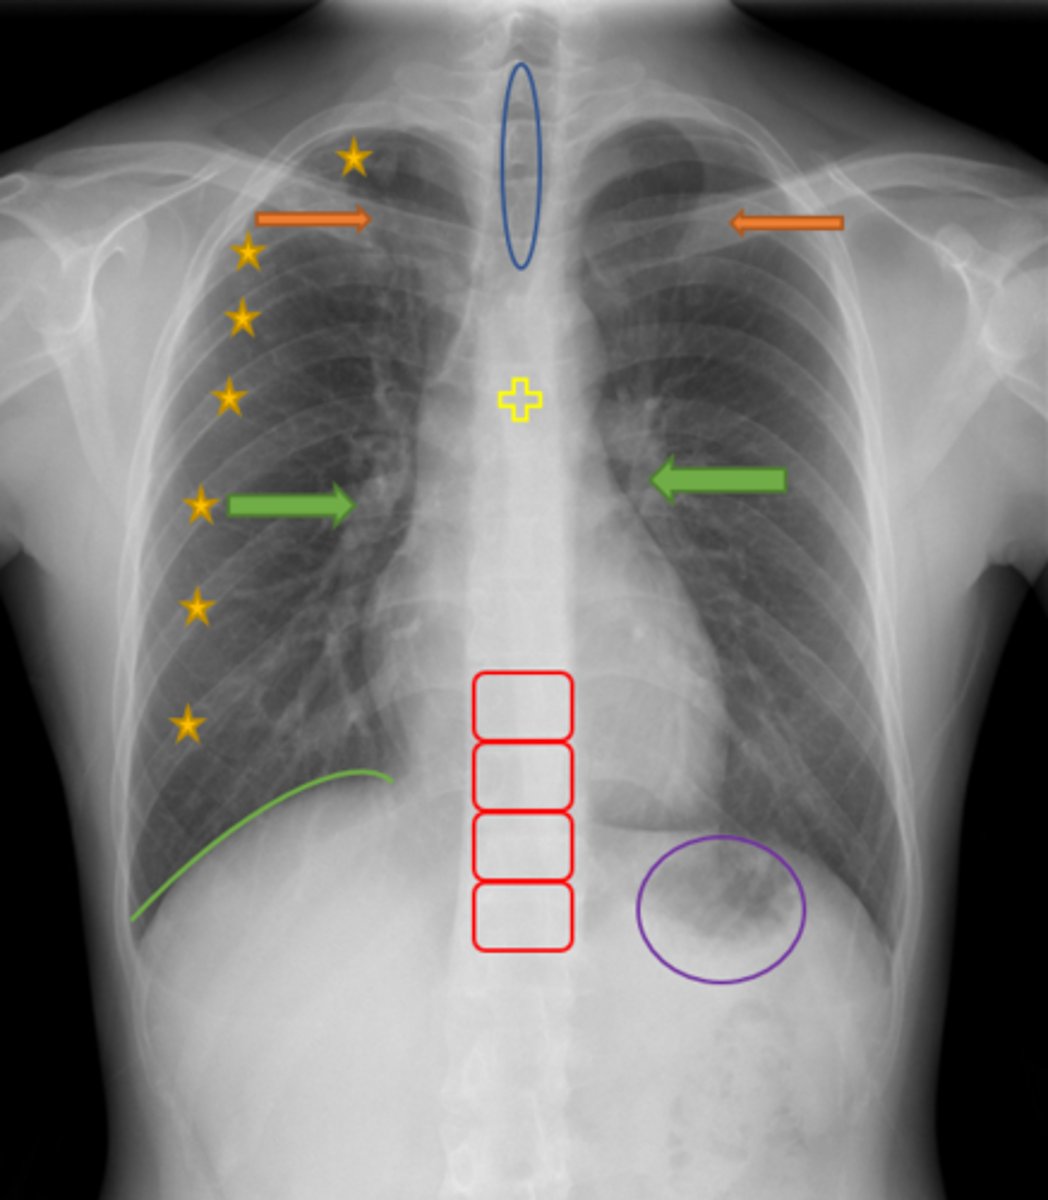

Aortic knob/arch

Pink Arrow

Left ventricle and border of the heart

Purple Line

Pulmonary arteries

Blue Arrows

Normal film

Interpretation

Trachea

Blue Oval

Pulmonary arteries

Green Arrows

Vertebrae/spine

Red Blocks

Clavicle

Orange Arrows

Ribs

Yellow Stars

Diaphragm

Green Line

Gastric bubble/stomach

Purple Circle

Carina

Yellow Cross